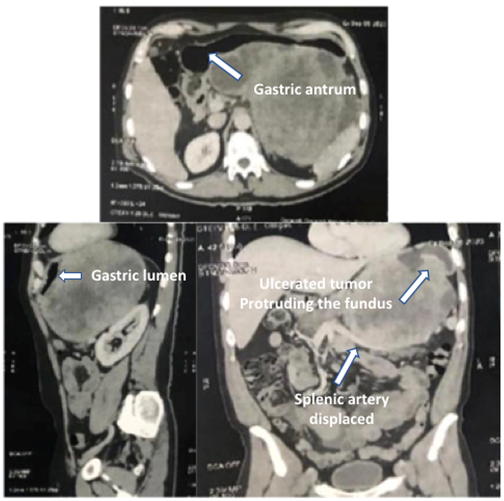

The ultrasound showed a large solid abdominal mass in the upper abdomen. The computed tomography reported a solid tumor with dimensions of 223.1mm X 142.9mm with peripheral vascularity, central necrotic areas, and displacement of splenic artery and biliary sludge. (Figure 1) The endoscopy revealed an ulcerated tumor that extended from the cardia to the posterior part of the upper third of the body of the stomach. The biopsy confirmed gastrointestinal stromal tumor (GIST). Therefore, informed consent was obtained for the surgical procedure and he was scheduled for tumor resection and cholecystectomy.

The esophago-gastroduodenal series taken a week after surgery (Figure 4) showed acceptable reconstruction of the stomach, without leaks, and adequate passage of contrast media.

Figure 4 Esophago-gastroduodenal series taken a week after surgery with acceptable gastric reconstruction forming an upper gastric tube.